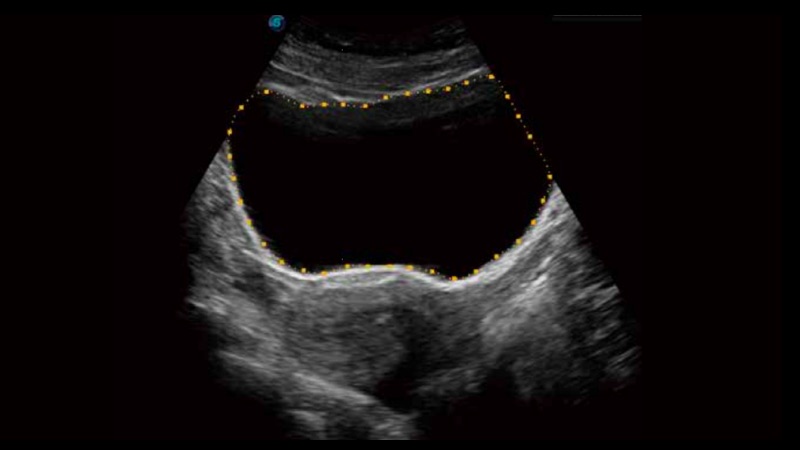

• 膀胱自动测量Auto Bladder

膀胱自动测量,一键式膀胱壁追踪和容量测量可有效提供更精确的轮廓和结果,不受膀胱形状和大小的影响。